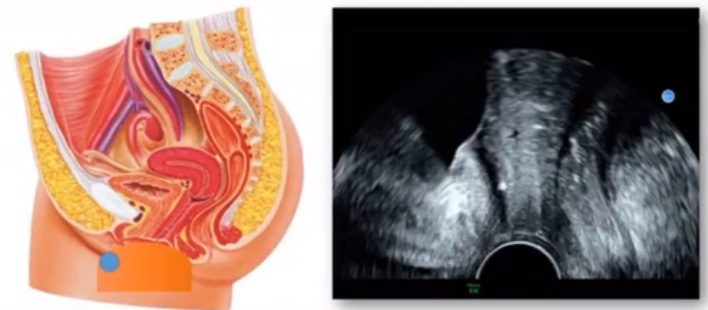

位于輸卵管的后下方,子宮兩側(cè)的后上方;借卵巢系膜與子宮闊韌帶后層相連。正常成人卵巢約4x3x2cm,跟睪丸的數(shù)值差不多,都是性器官,絕經(jīng)后卵巢萎縮變小、變硬。所以絕經(jīng)后婦女很難找到卵巢,主要功能:生殖和內(nèi)分泌功能分泌性激素。女性的第二性征。女性內(nèi)生殖器的血管分布,動(dòng)脈有子宮動(dòng)脈,卵巢動(dòng)脈,陰道動(dòng)脈,陰部?jī)?nèi)動(dòng)脈。靜脈它是與動(dòng)脈伴行。重要了解的是子宮動(dòng)脈,子宮動(dòng)脈是髂內(nèi)動(dòng)脈前干的重要分支,妊娠時(shí)候血流速度會(huì)增加的,為無(wú)創(chuàng)性檢查胎盤(pán)血管阻力的方法。未孕期頻譜為高阻力低舒張波形;正常妊娠時(shí)血流速度增加,血流阻力下降。